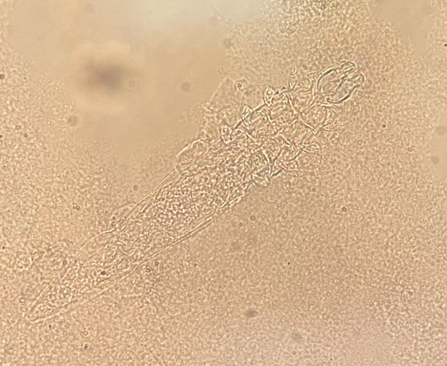

Demodex hair follicle mite